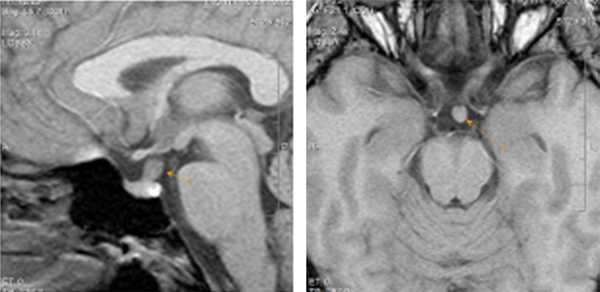

В центр МРТ Эксперт Воронеж обратилась пациентка, 31 год, с жалобами на головные боли справа и чувство тяжести в правых отделах шеи. Других жалоб пациентка не предъявляла, клинико-лабораторных данных о наличии дисфункции гипоталамо-гипофизарной системы предоставлено не было.

При проведении МРТ головного мозга

было выявлено умеренно выраженное утолщение и повышение интенсивности МР-сигнала от воронки гипофиза. Других изменений в проекции гипофиза, гипоталамуса, параселлярных областей не визуализировалось. Помимо этого, были обнаружены очаги глиоза больших полушарий головного мозга.

Данная картина в виде утолщения ножки гипофиза с достаточно четкими ровными контурами и повышение интенсивности МР-сигнала от нее характерна для заболевания воспалительной этиологии – лимфоцитарного гипофизита (когда происходит вовлечение в процесс воронки гипофиза, но при этом остаются интактными другие отделы гипофиза – адено- и нейрогипофиз). Среди других нозологий были выделены: а) инфундибулит другой этиологии, например при гранулематозном воспалительном процессе - саркоидозе б) вместе с тем, данные только МР-томографического исследовния, без достаточно четких клинико-лабораторных данных, не позволяют исключить и неопластического процесса данной локализации, в частности герминомы; в) гамартома гипоталамуса также выставлялась нашими докторами в дифференциально-диагностический ряд; г) метастатическое поражение воронки гипофиза.

из выстроенного дифференциального ряда врачи исключили гамартому (поскольку для данной патологии характерны другие сигнальные характеристики при МР-исследовании, клинически она проявляется преждевременным половым созреванием, насильственным смехом и плачем,чего не было в данном случае). Также из диф. ряда было исключено метастатическое поражение воронки (четкость и ровность контуров, симметричность, однородность, отсутствие узловатых утолщений – нехарактерные признаки для метастаза).

Дальнейшая дифференциальная диагностика

проводилась между гипофизитом (воспалительным процессом) и изменениями неопластического характера. В результате пришли к выводу, что выявленные изменения более специфичны для изменений воспалительного характера - лимфоцитарного гипофизита (в виде изолированного гипофизита). Но при этом полученная МР-картина не позволяет полностью исключить и неопластического процесса воронки гипофиза (герминомы) – что менее вероятно с учетом клинических данных и результатов внутривенного контрастирования.

Что дал метод МРТ в данном случае:

возможность выявить небольшой по размерам участок изменений в головном мозге, в воронке гипофиза (максимальный размер утолщенной воронки гипофиза всего 0,7 см), но при этом крайне важные клинически изменения, требующие дальнейшего наблюдение и, возможно, морфологической верификации .